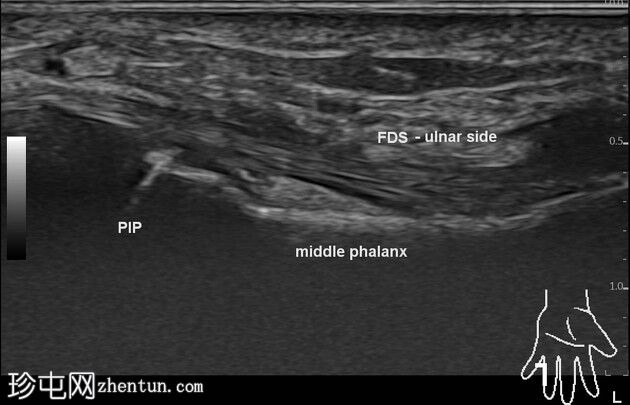

完整的屈指浅肌腱滑脱。连续短轴图像显示屈指浅肌腱向外侧延伸至深屈指肌。指深肌腱完好,附着于远端指骨撕脱的骨碎片(11 x 4 毫米)。它位于中节指骨远端骨干和指头水平。远端指骨掌侧短轴和长轴方向存在缺损。无腱鞘炎/关节积液。